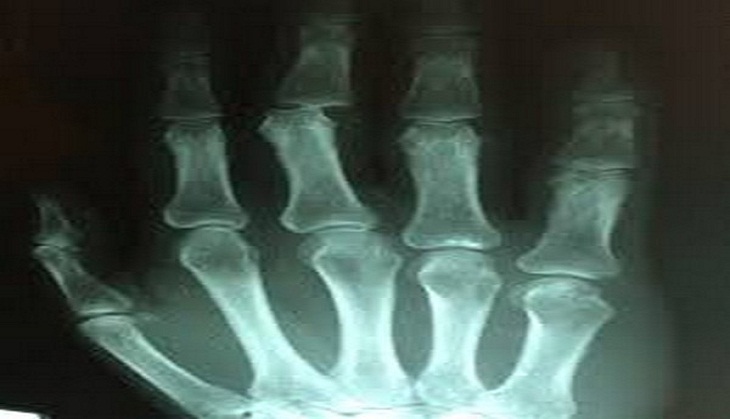

Removing old cells from joints can delay onset of osteoarthritis

Good news, a study has found that selective removal of old cells, senescent cells (SnCs) from joints can significantly delay the onset of osteoarthritis.

Their findings suggested that the selective removal of old cells from joints could reduce the development of post-traumatic OA and allow new cartilage to grow and repair joints.

Although these cells play an essential role in wound healing and injury repair, they may also promote cancer incidence in tissues. For instance, in articular joints, such as the knee and cartilage tissue, SnCs often are not cleared from the area after injury, thereby contributing to OA development.